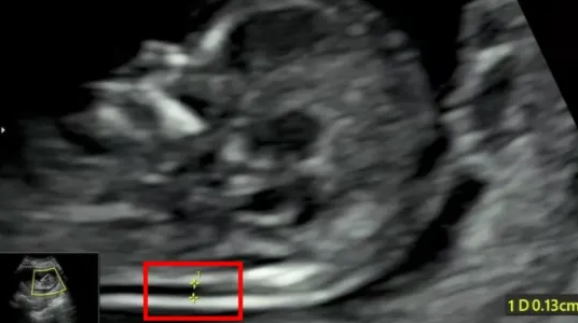

在为孕妈妈们做NT检查的同时,对于胎儿的结构也进行了详细的检查,并且发现了多例胎儿严重结构缺陷。

检查选在孕11~13周+6天进行,相当于头臀长45-84mm时测量,超过84mm检查结果会不准确。

NT增厚越明显,胎儿异常机会就越高,异常程度也会越严重。一般正常的NT厚度不能大于3mm,超过3mm表示NT增厚,存在异常可能。

NT异常增厚的主要原因,可能与胎儿染色体异常有关,比较常见的有2 1-三体、18-三体、13-三体综合征等;也可能是胎儿结构畸形,比如说心脏、骨骼系统发育的异常,但是相对于染色体异常来说,结构畸形或其他原因导致NT增厚占比较小。